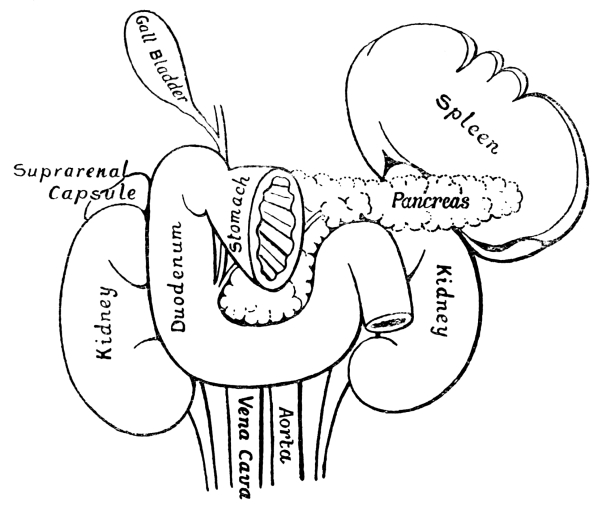

| 2. | The Organs of the Chest and Abdomen | xi |

| 6. | Duodenum and Neighbouring Organs | 99 |

The ribs from the first to the tenth have been cut across in the lateral line. The eleventh and twelfth ribs do not reach sufficiently far forwards to be cut. With the exception of a short segment near its junction with the ascending colon, the small intestine has been removed. The trachea is seen to divide into bronchi beneath the arch of the aorta. The right lung has three, the left two lobes. The kidneys are situate behind all the other viscera. On their upper ends rest the two suprarenal capsules. The lower edge of the right lobe of the liver follows closely the line of the ribs and costal cartilages. Below the left lobe of the liver the stomach comes to the anterior abdominal wall. The transverse colon (large intestine) comes to the anterior wall below the stomach. Below the latter the wall is in contact chiefly with coils of small intestine. The vermiform appendix rests on the posterior wall. Spleen and pancreas are not shown in the diagram.